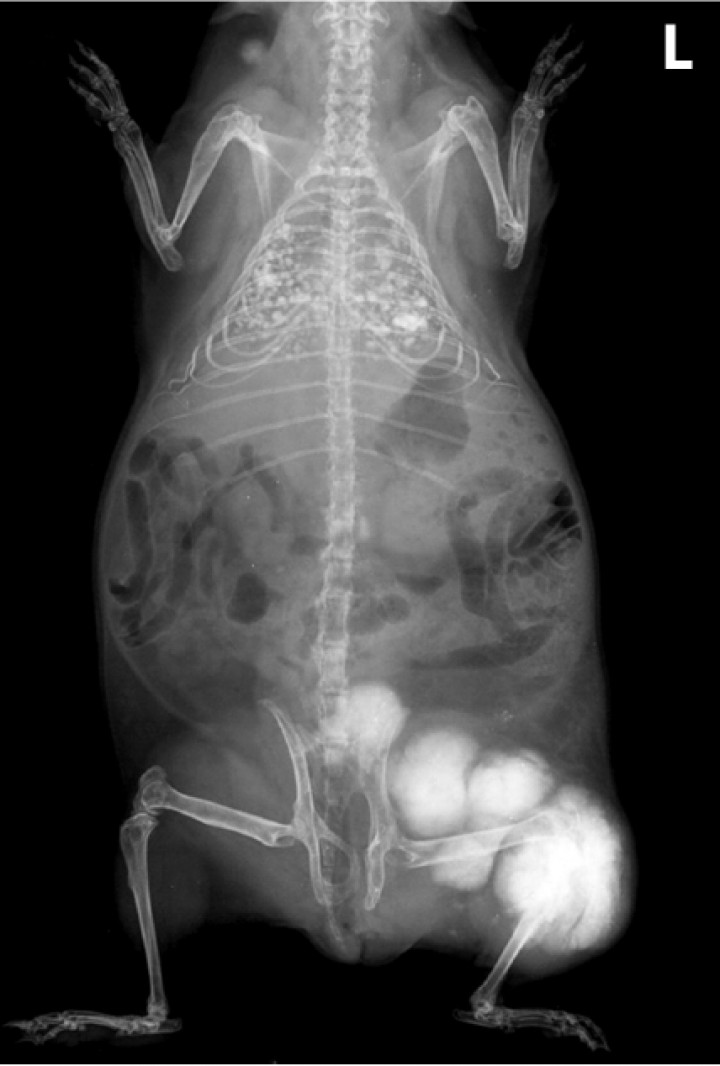

Las localizaciones de los condrosarcomas eran tibia y/o peroné (2 casos, ambos en su epífisis proximal y extendiéndose hasta la diáfisis) (Fig. 1), pelvis (1 caso), escápula (1 caso), dorso del cráneo (1 caso; Fig. 2) y en las últimas dos vértebras lumbares (1 caso). Una cobaya mostró múltiples masas óseas distribuidas desde la tibia/peroné hasta la zona lumbar caudal o coxal (Fig. 3), aunque la masa primaria involucraba aparentemente la epífisis proximal de la tibia y peroné, y alguna de las otras masas se interpretaron como posibles metástasis en ganglios regionales (lumbosacro, inguinal y/o poplíteo). Clínicamente, los animales presentaron anorexia o hiporexia (2 casos), apatía (1 caso), pérdida de peso (1 caso) y signos clínicos relacionados directamente con la localización de la neoplasia, como claudicación, ataxia, pérdida de propiocepción, disuria y dolor regional (cada uno de estos síntomas en una única cobaya). En una cobaya con metástasis pulmonares se observó disnea. En 4 cobayas se disponía de estudios radiológicos, que demostraban masas moderada o intensamente radiopacas (opacidad mineral) (salvo en la cobaya 6 [Fig. 1]), las cuales se originaban en las corticales primarias con invasión y osteolisis variable del hueso esponjoso (Figs. 1, 2B y 3). En 2 cobayas se apreciaron numerosos nódulos pulmonares de pequeño tamaño y opacidad similar a las masas óseas (Fig. 3). Una de estas cobayas (caso 1) mostraba además un nódulo similar en la zona inguinal, interpretado como una posible metástasis en ganglio regional (Tabla 1).

<p>Cobaya 4. Imagen radiológica de un condrosarcoma avanzado con múltiples masas desde la tibia/peroné (presumible masa primaria) hasta el coxal o zona lumbar caudal, así como metástasis numerosas en ambos pulmones. L: izquierda.</p>

Figura 3

Cobaya 4. Imagen radiológica de un condrosarcoma avanzado con múltiples masas desde la tibia/peroné (presumible masa primaria) hasta el coxal o zona lumbar caudal, así como metástasis numerosas en ambos pulmones. L: izquierda.